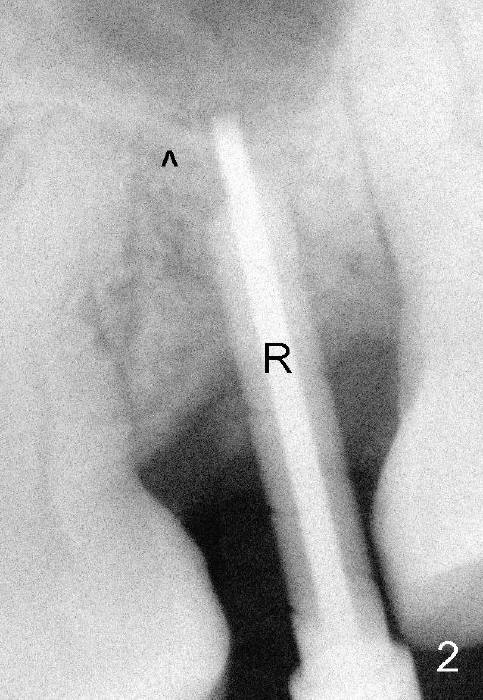

Exam immediately prior to surgery shows that the edentulous ridge is wide buccolingually. The mesiodistal space is less than 6 mm. It appears that a 4 mm implant is appropriate. Two piece implant is chosen over a one-piece one, because of large surface area of the former. After local anesthesia, a 3.5 mm tissue punch is used for access to the bone. A 1.5 mm pilot drill initiates osteotomy 8 mm in length (Fig.1 D). The drill is more or less in the middle of the edentulous space and 1 mm coronal to the sinus floor (^). Then a 2 mm pilot drill, 2.5 mm and 3 mm reamers are used to enlarge osteotomy (8 mm deep). Mixture of autogenous bone and Osteogen and 2.5 mm Bicon osteotome are used for sinus lift. The osteotome does not reach the intended depth of 10 mm. The osteotomy is extended with the 2 mm drill and 2.5 mm reamer (Fig.2 R) to barely perforate the sinus floor. When a 4x11 mm implant is being placed, it tends to deviate distally. The implant is backed up twice: initially it appears to lean mesially, but as it is seated deeper, it is deviated distally again (Fig.3). An immediate provisional has to be fabricated to prevent the space from further narrowing. A 3.5x3 mm abutment is placed. The mesial surface of the tooth #14 (Fig.4 black area) is trimmed for restoration. Why is the implant deviated? How to fix it?